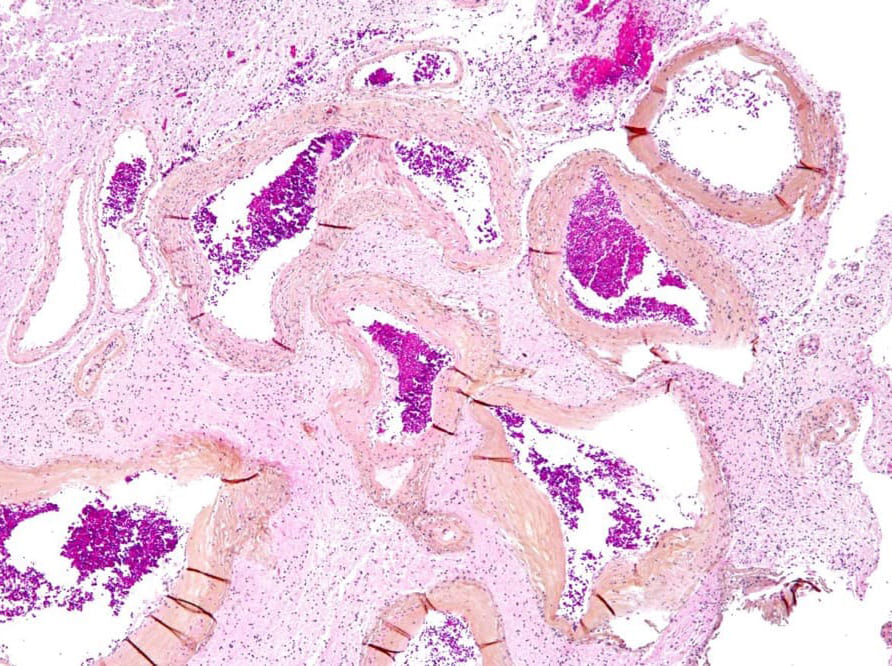

脳動静脈奇形における病理所見:多数の血管内皮細胞

(出展:Libre Pathology / Vascular Malformation)